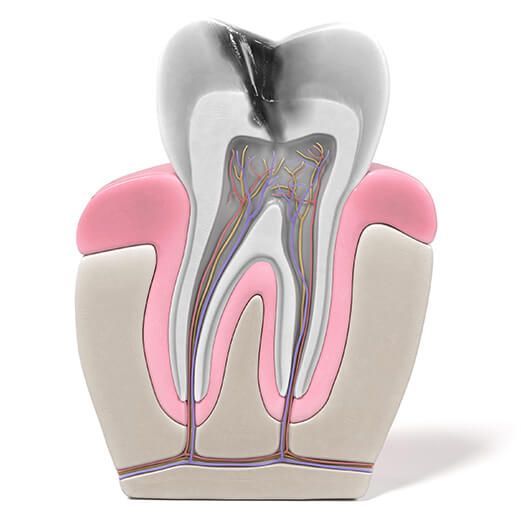

What Is a Root Canal?

Root canal treatment is the process of devitalizing the tooth by removing the dental pulp affected by inflammation/infection, causing pain. The procedure is necessary to alleviate discomfort, cure the infection, and preserve the tooth’s function for years to come.